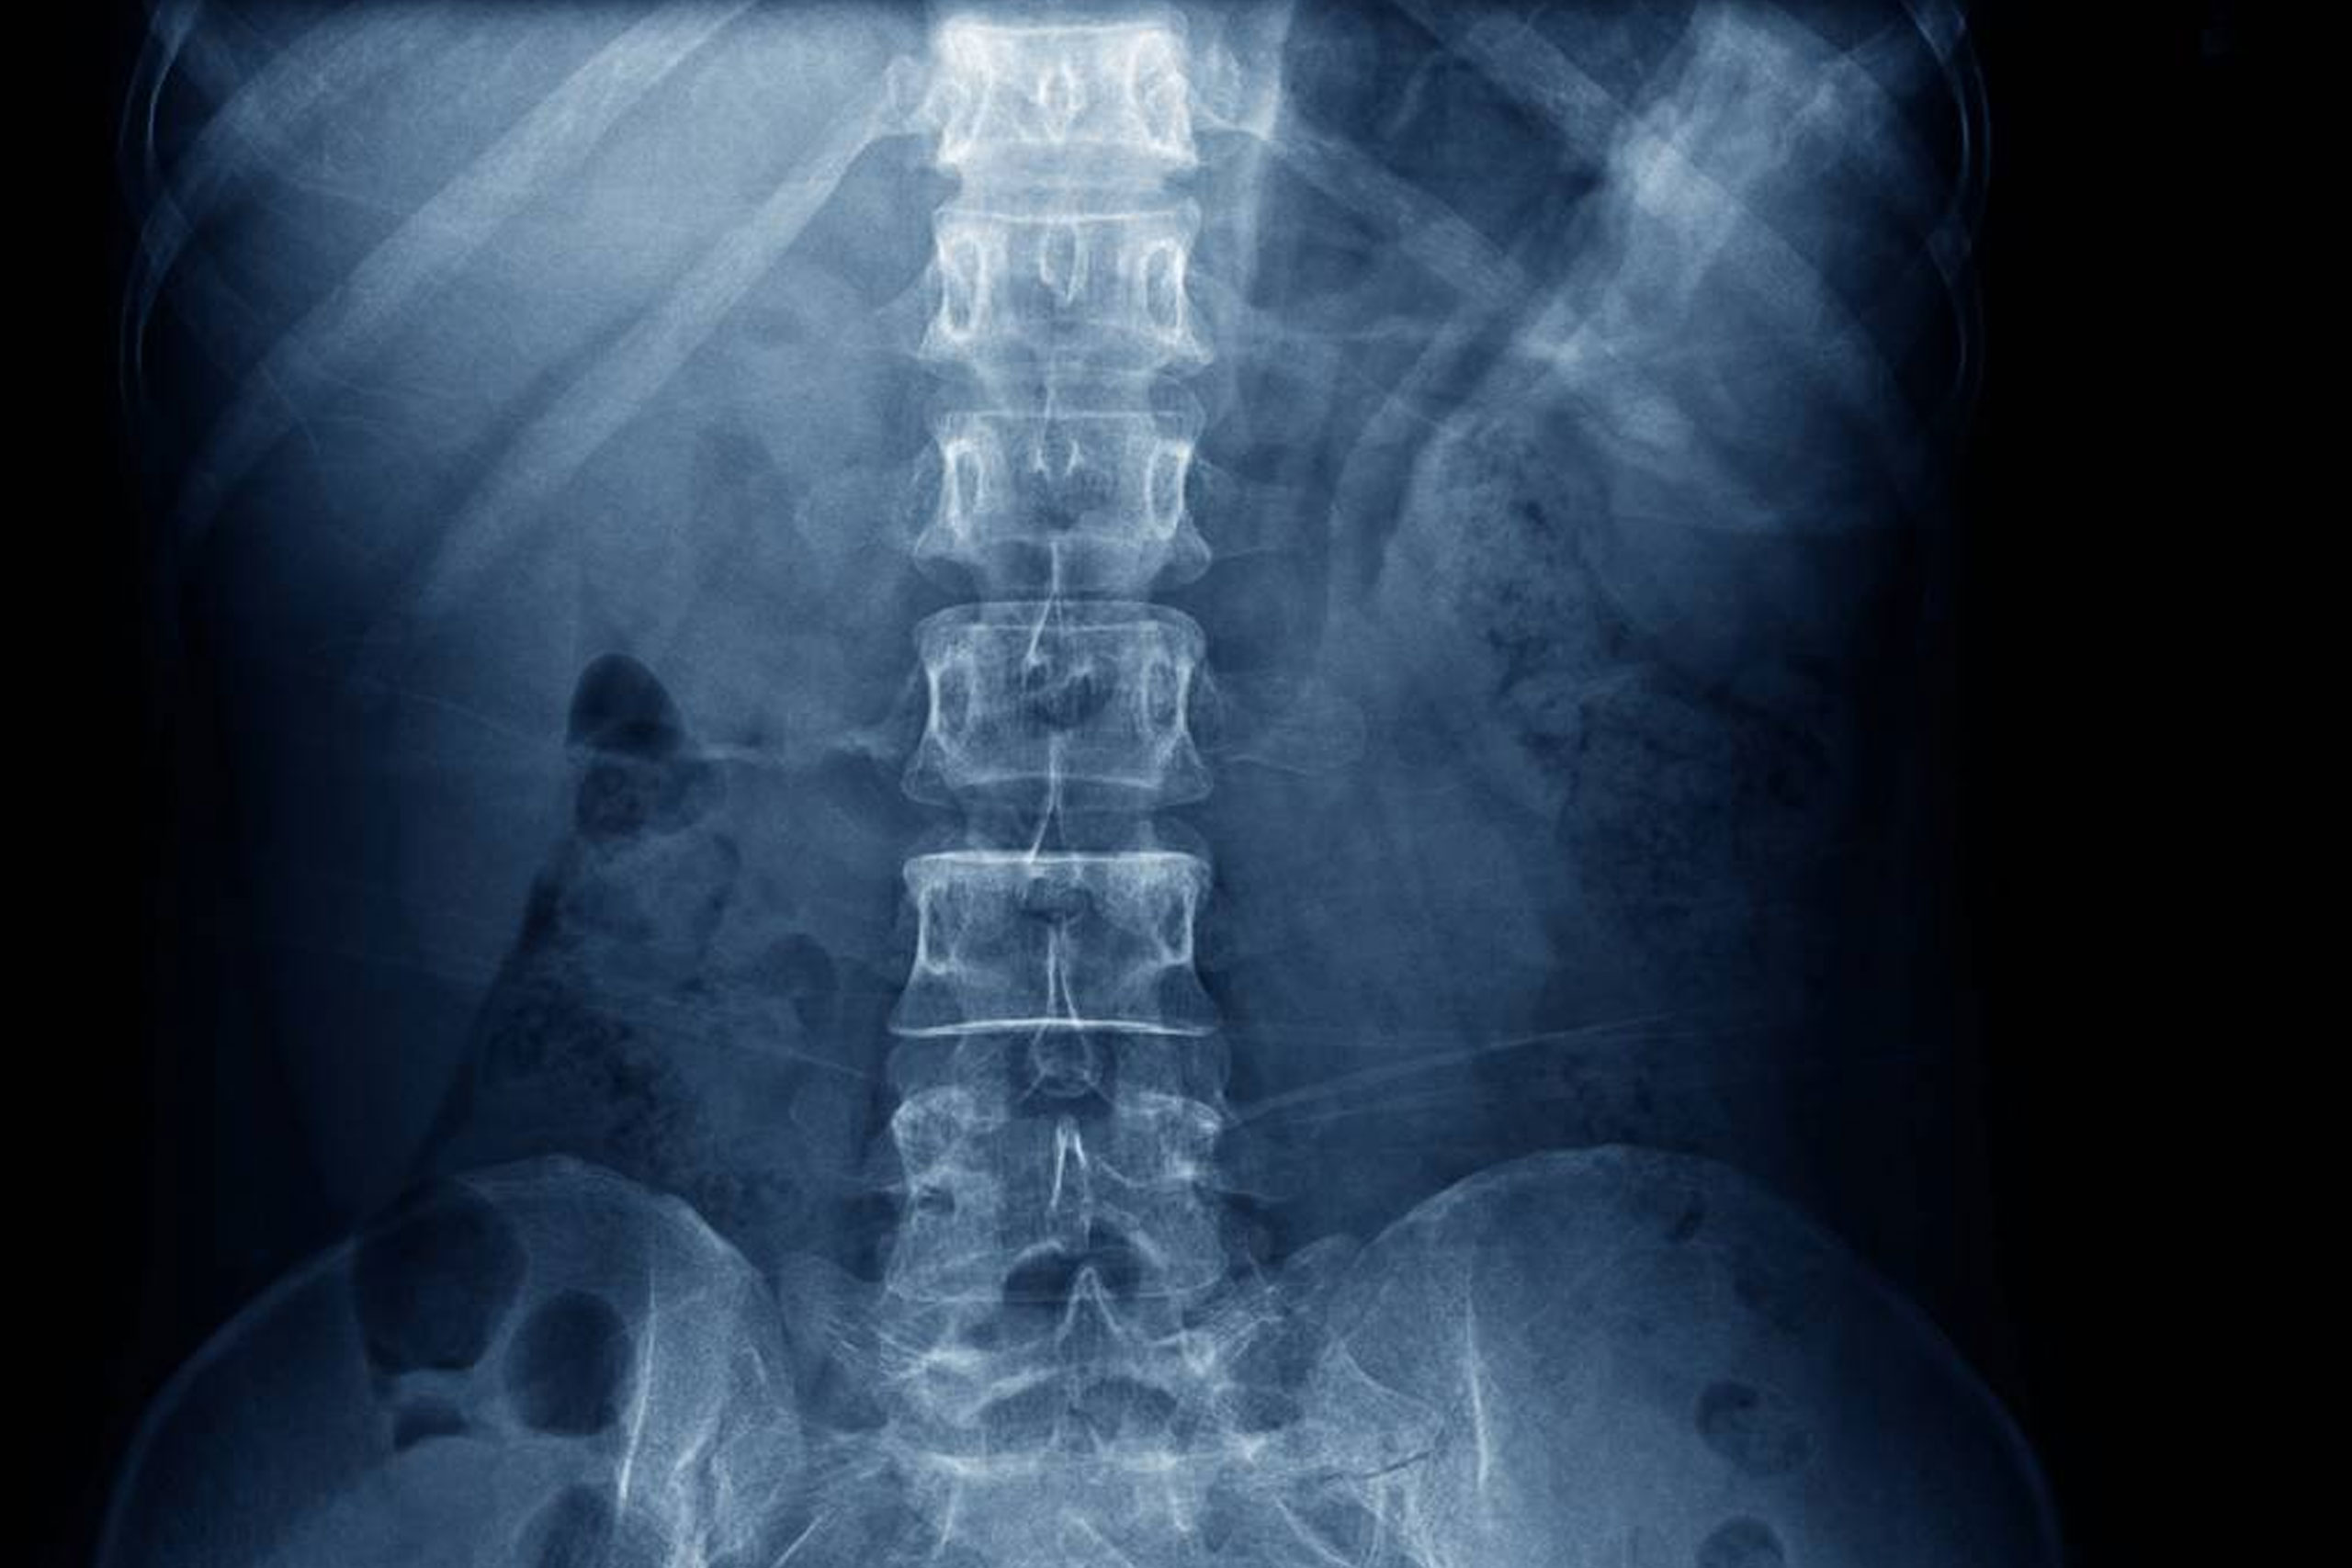

A transforaminal epidural injection is a specific type of epidural injection aimed at delivering medication directly into the epidural space near a spinal nerve root. This procedure is often used to relieve pain caused by conditions such as herniated discs, spinal stenosis, or radiculopathy. Because this injection needs imaging guidance for precise delivery of the medication, this procedure has to be done at a local surgery center. This injection can be an effective option for patients looking to manage pain without surgery. It’s important to discuss the procedure, benefits, and risks with a healthcare provider to determine if it’s the right choice for your situation.

2. Fluoroscopy Guidance: Real-time imaging (fluoroscopy) is often used to precisely locate the target area where the nerve root exits the spine.

3. Injection: A needle is carefully inserted into the transforaminal space (the area where the nerve exits the spinal column). Once the needle is in place, a small amount of contrast dye may be injected to confirm proper placement.